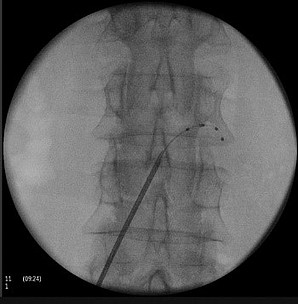

Vor allem bei bestimmten Schmerzsyndromen, die nicht oder nicht mehr ausreichend auf eine medikamentöse Therapie ansprechen, ist es möglich, durch die Rückenmarksstimulation eine Schmerzlinderung zu erzielen. Hierbei werden feine Elektroden in den Rückenmarkskanal eingesetzt, die elektrische Impulse abgeben. Das Einbringen der Elektroden kann in örtlicher Betäubung erfolgen. Die Elektroden werden durch einen Impulsgeber angesteuert, der unter die Haut am Gesäß oder an der Bauchwand der Patient:innen implantiert wird. Die abgegebenen elektrischen Impulse hemmen die Schmerzweiterleitung. Die Schmerztherapie durch Rückenmarksstimulation findet Anwendung nach Verletzung von Nerven oder des Rückenmarkes, aber auch bei Phantomschmerzen und bei behandlungsresistenten Schmerzen durch Durchblutungsstörungen bei Herzkrankheit (Angina Pectoris) und Gefäßkrankheit der Beine (pAVK). Bei der Gefäßkrankheit der Beine (pAVK) kann die Stimulation zudem dazu beitragen, die Durchblutung wieder zu verbessern und die Gliedmaßen zu erhalten. Die Nervenstrukturen bleiben bei der Rückenmarksstimulation erhalten, sodass die Stimulation jederzeit rückgängig gemacht werden kann. Die Einstellungen des Impulsgebers lassen sich von außen – auch durch die Patient:innen – verändern, sodass die Stimulation jederzeit an die Bedürfnisse der Patient:innen angepasst werden kann.